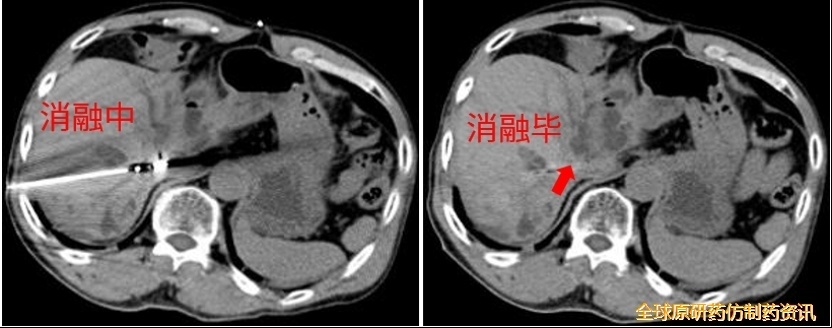

CT消融过程中,消融针从门-腔间隙穿透肿瘤;

消融毕,术区呈条状密度增高灶,相邻胆管、血管无扩张、积气。

图10 第四次消融示意图